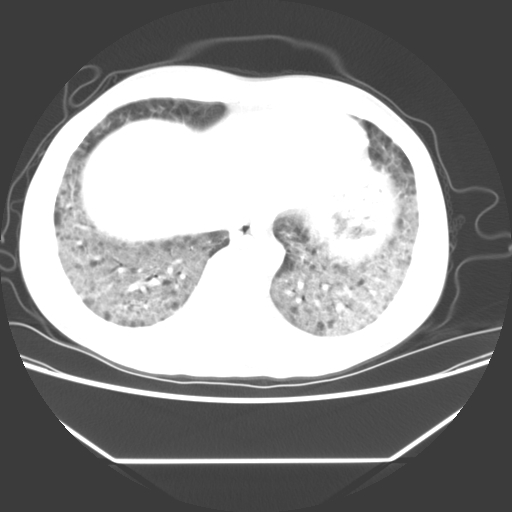

病人55岁,咳嗽,胸闷

忘了传病史了,病人55岁,咳嗽,胸闷

两肺部呈“毛玻璃”状改变,原因待查考虑感染性病变

病人是否发烧,两肺“磨玻璃”影,其间见空气支气管征和碎路石征。考虑肺泡蛋白沉着症。

两肺广泛对称磨玻璃样影,密度不均,考虑机遇性肺部感染。

双肺弥漫磨玻璃样病变,病史很重要。有感冒或发烧史,甲流不除外。无发烧可考虑肺泡蛋白沉积,但肺泡蛋白沉积边缘往往较清晰,与正常肺组织分界清晰

两肺弥漫间质性病变,考虑肺泡蛋白沉着症。建议进一步检查。

两肺“磨玻璃”影,其间见空气支气管征和碎路石征。考虑肺泡蛋白沉着症。

两肺部呈“毛玻璃”状改变,支持肺泡蛋白沉着症。